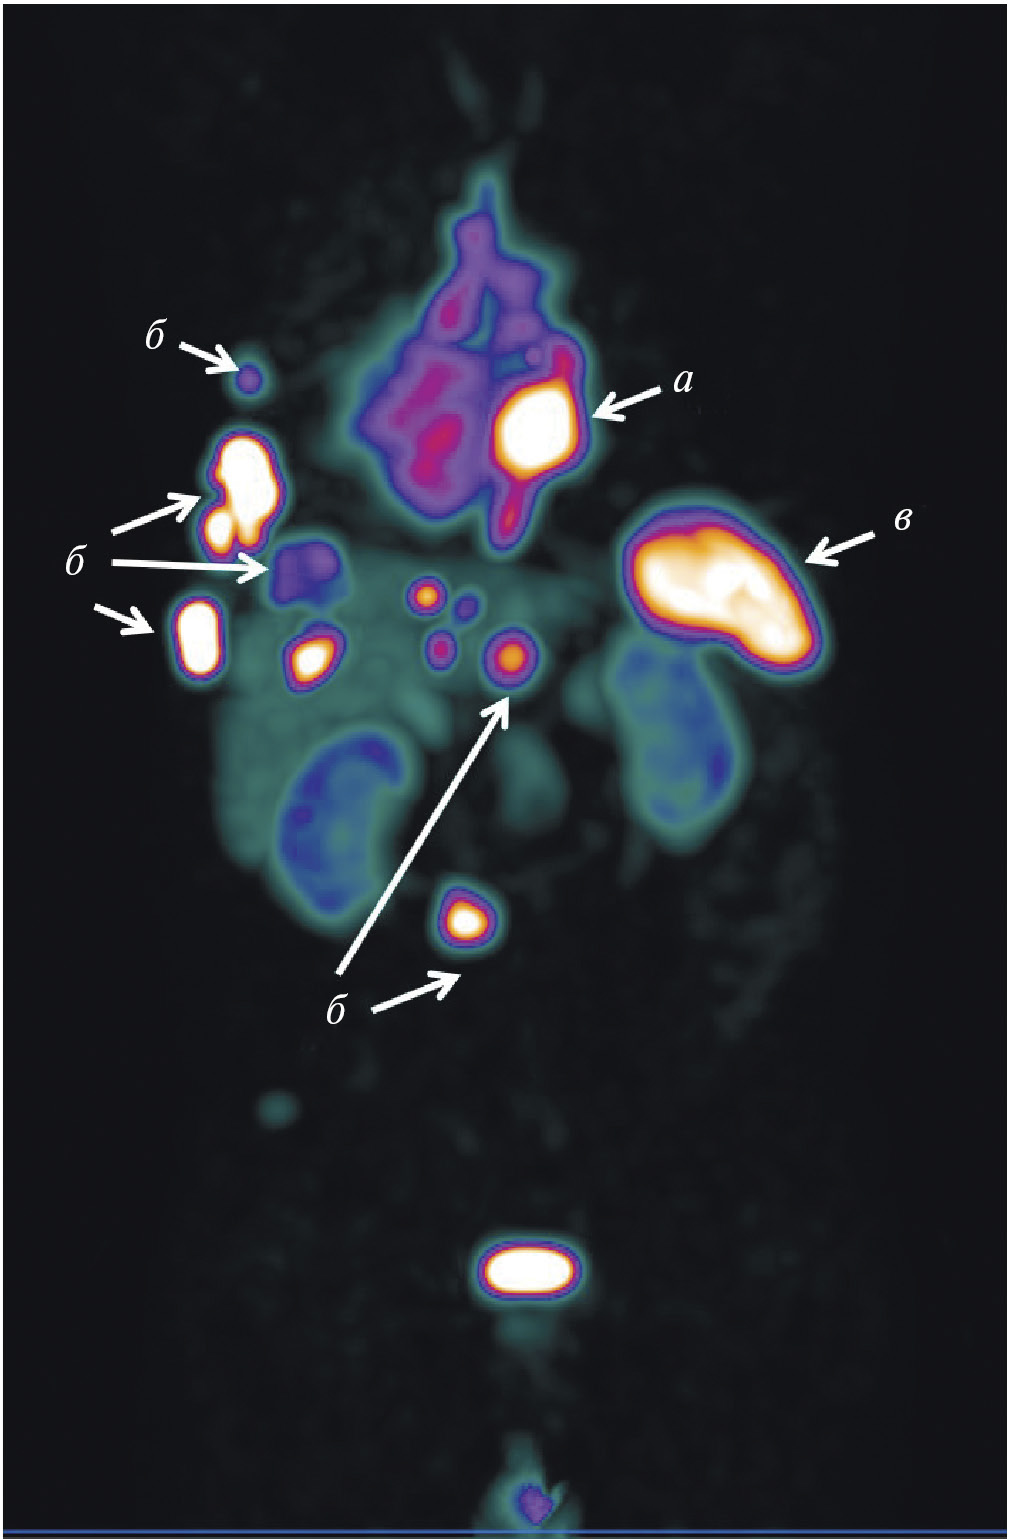

В мировой ядерной медицине для сцинтиграфии обычно применяют 111In-пентетреотид, или 111In-октреотид ([111In-DTPA]octreotide, OctreoScan, Tyco Healthcare, США; АО “Фармсинтез”, Россия). Основные показания к его использованию — стадирование, рестадирование и мониторинг лечения нейроэндокринных SSTR-позитивных опухолей. В последние годы 111In-пентетреотид служит для радионавигации при хирургическом лечении новообразований с гиперэкспрессией соматостатиновых рецепторов. К сожалению, физические характеристики индия-111 (длительный период полураспада, неоптимальный для регистрации на гамма-камере спектр излучения, высокая стоимость циклотронного производства) ограничивают его применение в радионуклидной диагностике. В связи с этим не подвергается сомнению актуальность создания в России меченного технецием-99м октреотида для ОФЭКТ-диагностики нейроэндокринных опухолей. Разработкой такого радиофармпрепарата в рамках проекта федеральной целевой программы “Фарма-2020” занимался ТПУ в сотрудничестве с НИИ онкологии Томского НИМЦ. Клинические испытания отечественного 99mТс-октреотида продемонстрировали его высокую эффективность при диагностике и стадировании НЭО (рис. 3). В настоящее время набор для приготовления этого РФЛП зарегистрирован в России под названием “Нейроскан, 99mТс”, а его производство налажено в ТПУ.

Рис. 3. ОФЭКТ/КТ с 99mТс-октреотидом пациента с нейроэндокринным раком лёгкого: а — конгломерат первичной опухоли и метастазов в лимфатические узлы; б — метастазы в кости; в – селезёнка